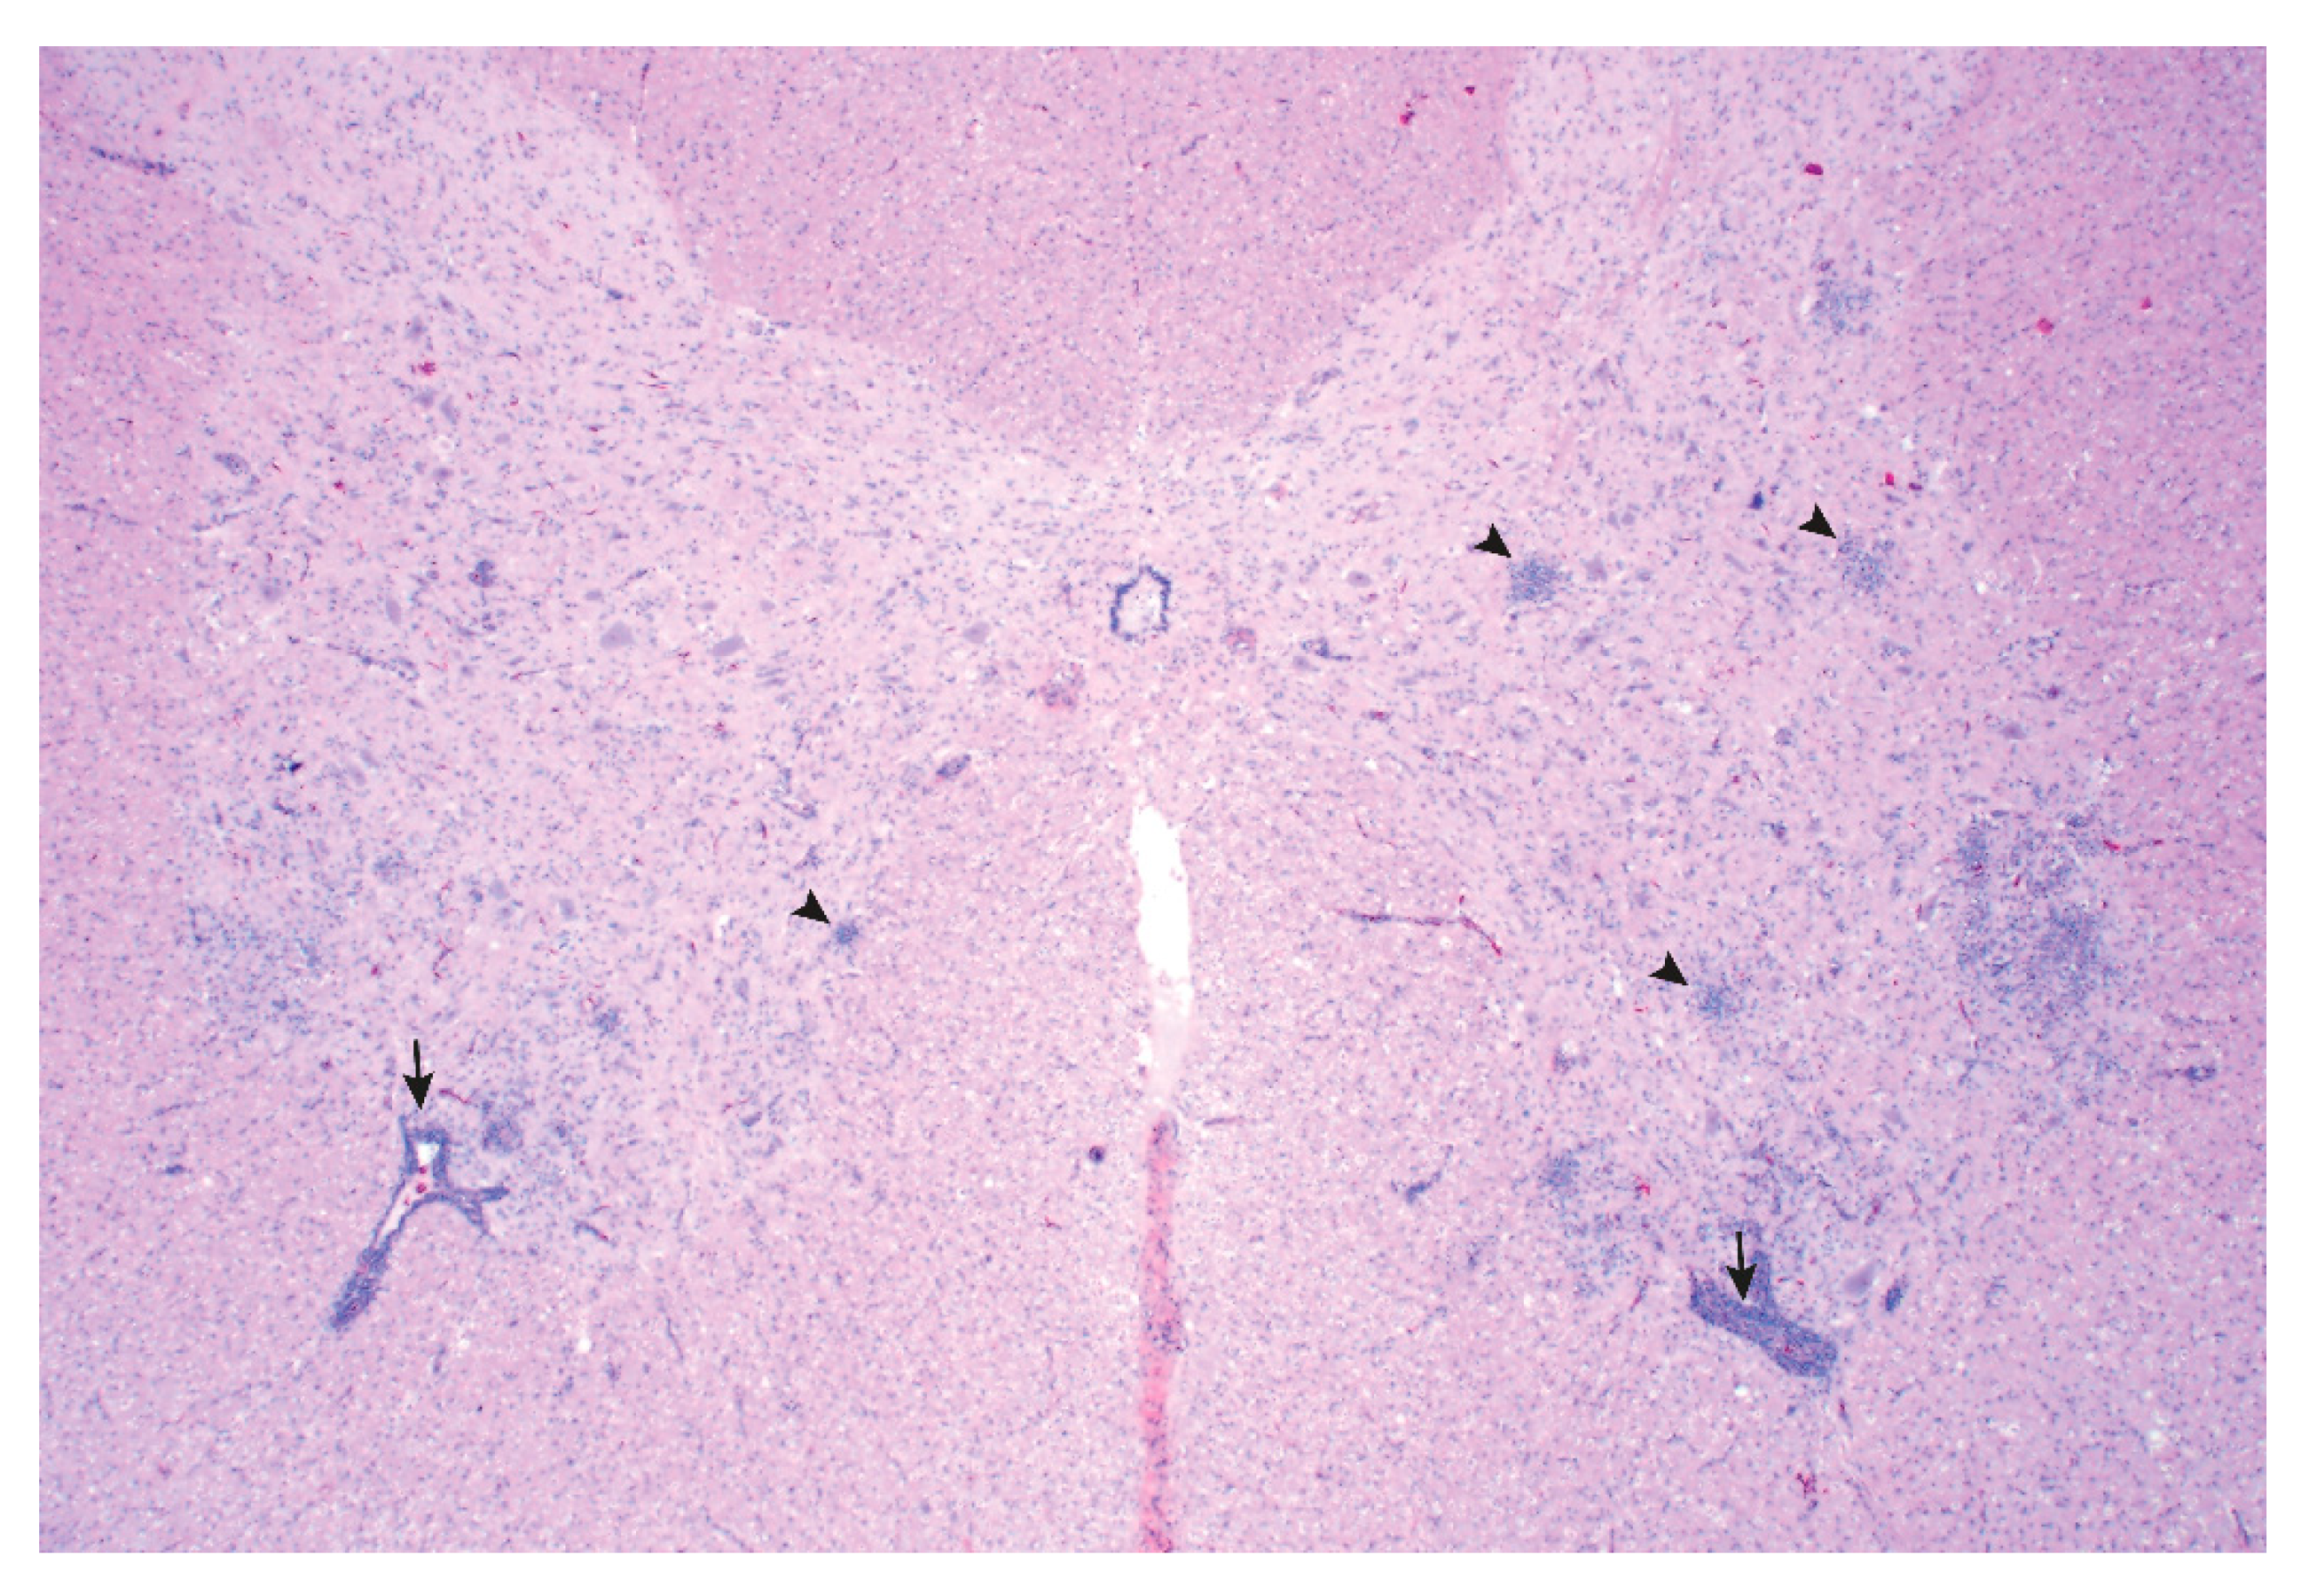

- Arruda, B.; Arruda, P.; Hensch, M.; Chen, Q.; Zheng, Y.; Yang, C.; Gatto, I.R.H.; Matias, F.F.; Gauger, P.; Schwartz, K.; et al. Porcine Astrovirus Type 3 in Central Nervous System of Swine with Polioencephalomyelitis. Emerg. Infect. Dis. 2017, 23, 2097–2100. [Google Scholar] [CrossRef]

- Matias, F.F.; Bradner, L.K.; Burrough, E.R.; Cooper, V.L.; Derscheid, R.J.; Gauger, P.C.; Harmon, K.M.; Madson, D.; Piñeyro, P.E.; Schwartz, K.J.; et al. Polioencephalomyelitis in Domestic Swine Associated with Porcine Astrovirus Type 3. Vet. Pathol. 2019, 57, 82–89. [Google Scholar] [CrossRef]

- Rawal, G.; Matias, F.F.; Macedo, N.R.; Bradner, L.K.; Harmon, K.M.; Mueller, A.; Allison, G.; Linhares, D.C.L.; Arruda, B.L. Detection and Cellular Tropism of Porcine Astrovirus Type 3 on Breeding Farms. Viruses 2019, 11, 1051. [Google Scholar] [CrossRef]